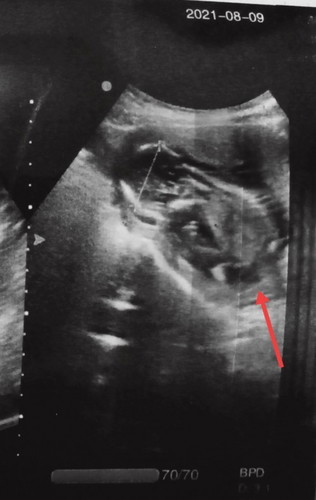

Saya lgi hamil 25 week.. tadi pas bab keluar darah bun.. tapi ngga sakit sama sekali.. Baru kali ini bab keluar darah ,lumayan agak bnyk. Tpi pas bab selesai juga gk keluar lgi drhnya.. biasanya ngga sampe keluar darah cuma ambyen nya yg keluar. Itu ngaruh buat baby nggak ya bun.. #seriusnanya #seriusnanya